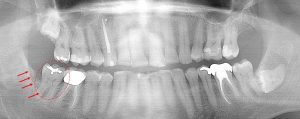

This 52 year old patient had the lower right 3rd molar extracted 6 years earlier due to a chronic infection. The boney defect (arrows) posterior to the 2nd molar (circled) is a site with a chronic gum infection present. Repeated cleaning is necessary to prevent further bone loss around the 2nd molar. Note the other two 3rd molars laying in the bone.